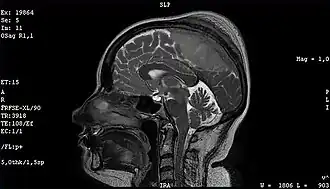

Опухоль

- опухоли нервной системы и оболочек мозга;